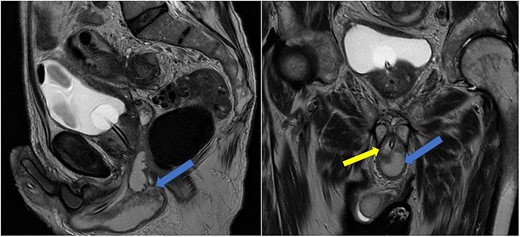

Case 1: sagittal and coronal T2-weighted images showing the collection (blue arrow) inferior to the prostate, and involving the corpus spongiosum (yellow arrow).

Imaging was suggestive of an infected Cowper’s syringocele. As the patient was clinically stable, a trial of antibiotic therapy was suggested. Repeat MRI a week later showed that the collection had extended into the corpus spongiosum, which now appeared expanded with the fluid density signal (Fig. 1). On a review, the urethral catheter was thought to be impairing potential drainage of the collection. It was removed, and a suprapubic catheter was inserted. Ultrasound guided aspiration failed to drain a significant amount of pus, which also grew S. anginosus. There was also radiological suspicion of a colovesical fistula. The patient was reviewed by the colorectal surgeons, who felt that as there were no other symptoms relating to the fistula, and the patient was physiologically frail, and defunctioning of the bowel would be inappropriate. Likewise, the patient was deemed too frail for any surgical management of the collection. He was discharged after a total of 6 weeks’ antibiotics. Repeat MRI 4 months later (Fig. 2) showed a smaller but persistent collection.